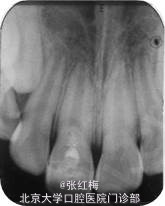

X线示:11、21发育9期,根管粗大,未见明显根折线,根尖周未见病变影,骨硬板清晰,未见牙槽突骨折线;

检查:11充填体完好,叩(-),不松,龈未见异常,X线:11根尖继续形成中,根周膜清 晰;

检查:11粘接断冠完好,叩(-),不松,龈未见异常,冷测有感觉,无疼痛;X线:11根 尖继续

形成中,根周膜清晰